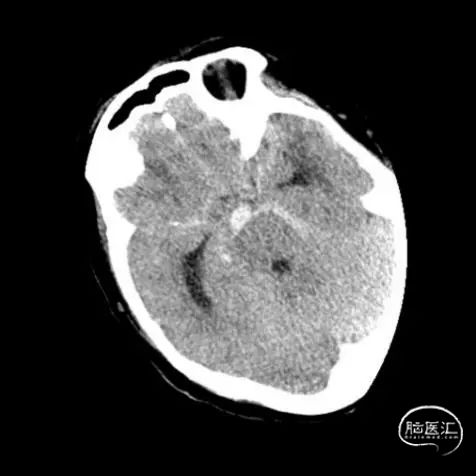

入院后立即行脑血管造影提示椎基底冗长扩张(基底动脉脑桥部分最宽处约5.2mm),伴有基底动脉多发动脉瘤,基底动脉尖动脉瘤(最大径约8mm)伴子囊和基底动脉下段动脉瘤(最大径约11mm)(图2)。